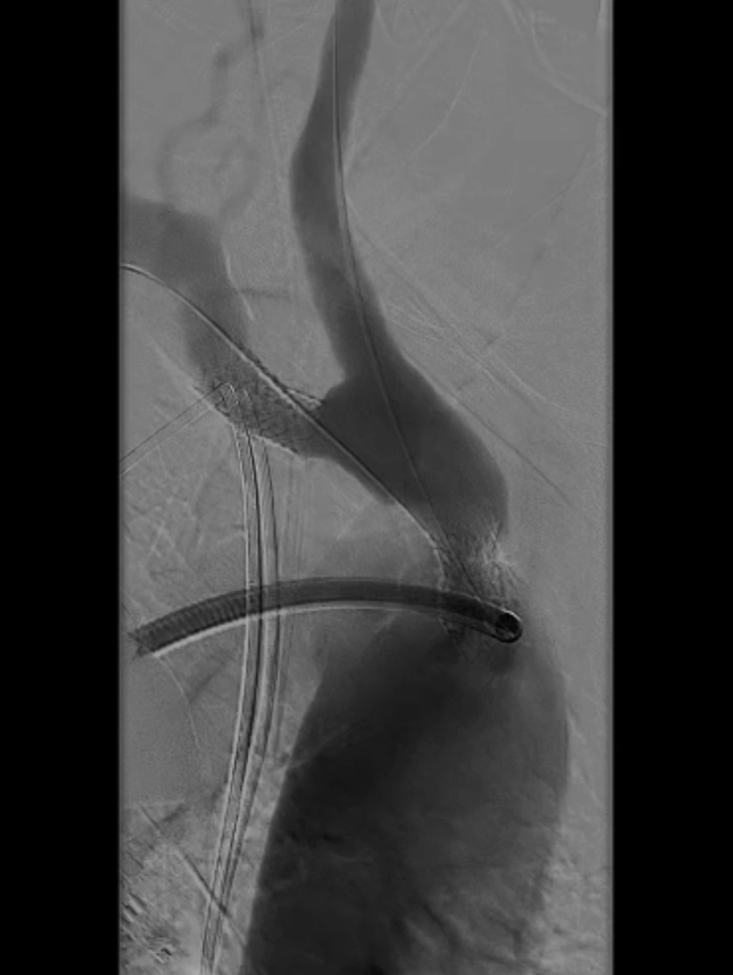

球囊扩张:采用同轴双导丝技术,以4×40mm、6×40mm球囊逐级扩张狭窄段;造影发现残存狭窄后,再次用6×40mm球囊扩张。

4*40mm球囊扩张

无名动脉支架

多角度造影

仍有残存狭窄

6*40mm球囊扩张

再次6*40mm球囊扩张